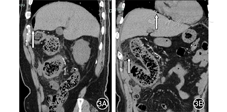

患者男,74岁,因"右侧腹部疼痛1个月,发热1 d"于2019-03-17入院浙江省衢州市人民医院。患者1个月来持续性腹部隐痛,右下腹为主,大便不成形,色黄,入院1 d前出现发热,达38.6℃,无畏寒。饮酒史40余年,日饮中药酒"五加皮酒"200 mL。入院查体:血压150/73 mmHg(1 mmHg=0.133 kPa),腹软,右侧腹压痛明显,无反跳痛,肝脾肋下未及,双下肢无凹陷性水肿。实验室检查:血红蛋白127 g/L,白细胞计数7.6×109/L,血沉55 mm/h,C-反应蛋白101.52 mg/L,血清白蛋白31.6 g/L,球蛋白35.5 g/L,血清降钙素原0.63 ng/mL;大便隐血(+);肝炎系列、肿瘤标志物检查均无异常,结核抗体阴性。心电图正常。腹部超声:肝、胆、胰腺未见异常。结肠镜检查:肠腔黏膜充血水肿、灰暗,糜烂从回盲部至乙状结肠均有,升、横结肠皱襞消失,溃疡附着有脓性分泌物(图1)。肠镜活检病理:(升结肠)黏膜慢性炎伴坏死。腹部CT平扫:升、横结肠管壁明显增厚水肿,四周脂肪间隙模糊,系膜血管钙化,考虑缺血性肠病。门静脉CT血管成像:门静脉主干走形正常,管腔内无充盈缺损影;右半结肠静脉管壁见多发点状、细条状钙化影,相应结肠管壁增厚,考虑为静脉硬化性肠炎(图2)。入院后予抗炎,丹参川芎嗪注射液、前列地尔注射液改善微循环等治疗。次日热退,腹痛逐渐好转,复查C-反应蛋白14.90 mg/L,谷丙转氨酶18.3 U/L,血清降钙素原0.22 ng/mL。住院8 d出院。出院诊断:特发性肠系膜静脉硬化性肠炎(idiopathic mesenteric phlebosclerosis,IMP)。嘱戒酒。电话随访,患者未戒酒,时有腹部隐痛,大便稀糊。出院26 d因"突发腹痛5 h余"急诊入院。查体:痛苦面容,腹肌明显紧张,显著压痛,伴反跳痛,以右侧腹部为著,听诊肠鸣音未闻及。急诊全腹部CT平扫:膈下及上腹腔游离气体,消化道穿孔考虑;结肠肝曲肠壁增厚,四周有明显渗出,周围系膜血管多发钙化(图3)。实验室检查:C-反应蛋白126.62 mg/L。急诊手术:切开腹膜见腹腔淡血性积液及气体逸出,积液100~120 mL,探查见盲肠向升结肠方向明显弯曲,升结肠偏下方结肠破裂,破口大小约3.5 cm,间断有大便自破口溢出,升、横、降结肠广泛发黑、挛缩、水肿,其中以升结肠为著,伴多发性地图样坏死灶。行右半结肠切除和回肠造瘘术。大体病理:见切除右半结肠肠管长26 cm,近回盲部肠管增粗,最大径7.5 cm;剪开肠管有大量粪便潴留,皱襞消失,结肠肠壁增厚,浆膜面暗红色。镜检病理:(右半结肠)黏膜慢性炎伴出血,肠血管壁增厚、玻璃样变及钙化(图4),部分肠壁伴坏死;(肠周)14只淋巴结慢性炎。术后5个月后再次行结肠次全切除术加回肠造瘘回纳术,随访至今5个月,局部继发肠瘘,一般状况良好。

IMP尽管少见,但其在影像学尤其是腹部CT上有一定特色表现,典型病例提示受累结肠段增厚、僵硬,肠管及四周出现多发、细条状多发钙化,肠系膜上静脉分支可有不同程度细条状钙化。肠镜可见肠腔表面黏膜静脉曲张淤血,呈特殊暗紫色,触之易出血,结肠皱襞消失,伴有多发糜烂及溃疡[3,6]。

本例在确诊IMP后1个月出现结肠自发性穿孔破裂,紧急剖腹手术见盲肠向升结肠方向弯曲,升结肠偏下方结肠破裂,破口大小约3.5 cm,伴多发性地图样坏死灶。病理示肠血管壁增厚、玻璃样变及钙化,部分肠壁伴坏死。复习文献该病有少数肠坏死手术报告[1,9],但未见有结肠自发性穿孔至破裂。回顾患者结肠镜图像显示升、横结肠蓝色的水肿黏膜,溃疡深凿相邻而且有脓苔、粪质附着,肠皱襞消失;手术探查见盲肠向升结肠方向弯曲压迫,使此段结肠在肠系膜静脉广泛钙化基础上,静脉淤血、肠壁缺血加重,造成相邻溃疡坏死穿透,形成肠管破裂。此病例罕见,重视对IMP及其少见并发症的认识,及时正确处理是治疗成功的关键。